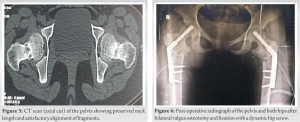

Computed tomogram (CT) scan of both hips confirmed a preserved neck length and alignment of fragments (Fig. 3). A diagnosis of bilateral stress fracture of the neck femur was made. Magnetic resonance imaging of both hips was done and the presence of osteonecrosis of the femoral head was ruled out. Under combined spinal and epidural anesthesia, the patient was taken on a traction table on both sides and both sides were operated in the same sitting, left followed by right. The fracture was reduced satisfactorily by a closed maneuver. However, as Powel’s angle was high on both sides, valgus osteotomy was planned at the sub-trochanteric level with an aim of getting 30° corrections in Powel’s angle on both sides. A guide wire was passed across the fracture from the lateral cortex of the trochanter at an angle of 100° to the long axis of the femur. Fixation of the fracture was done with a 9.5 mm dynamic hip screw (DHS). Thereafter, valgus sub-trochanteric osteotomy was performed on both sides and fixation was done with a 130° side plate (Fig. 4).